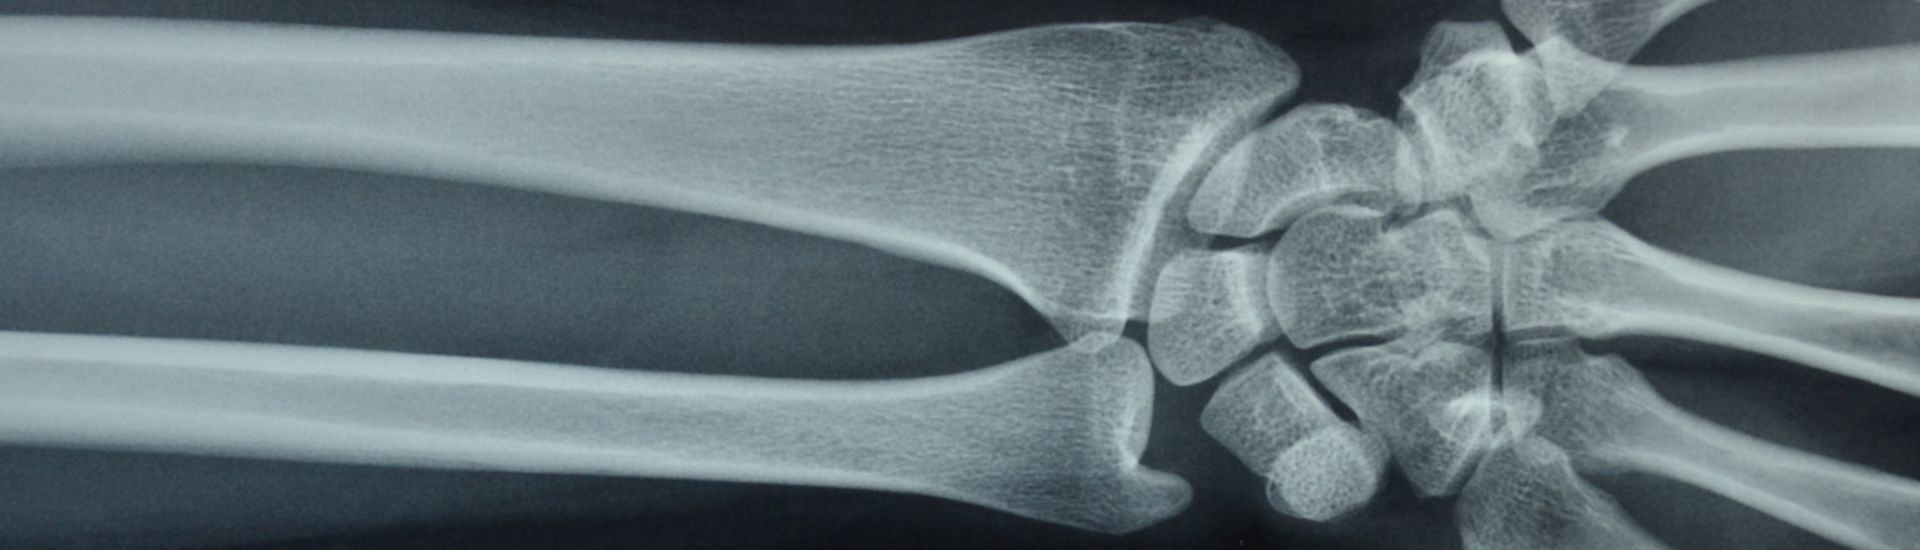

Durante un esame RX Polso, il paziente viene posizionato in modo da ottenere immagini nitide e dettagliate. Il polso viene esposto ai raggi X per pochi secondi, mentre il tecnico radiologo controlla l’apparecchiatura e cattura le immagini necessarie. Questo processo rapido e indolore permette ai medici del Poliambulatorio S-Medical Group di Sora di visualizzare con precisione la struttura ossea e articolare, individuando possibili problematiche e pianificando la terapia più adeguata.

Durante l’RX Polso, i raggi X attraversano i tessuti del polso e interagiscono con le diverse strutture interne. Questo processo di interazione permette ai raggi di trasferire energia ai tessuti, che viene poi catturata sotto forma di immagine radiografica. Le immagini risultanti offrono una visione chiara e dettagliata delle ossa e delle articolazioni, permettendo ai medici del Poliambulatorio S-Medical Group di Sora di valutare con precisione la situazione clinica del paziente.